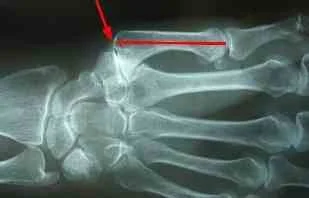

Intermetacarpal Block